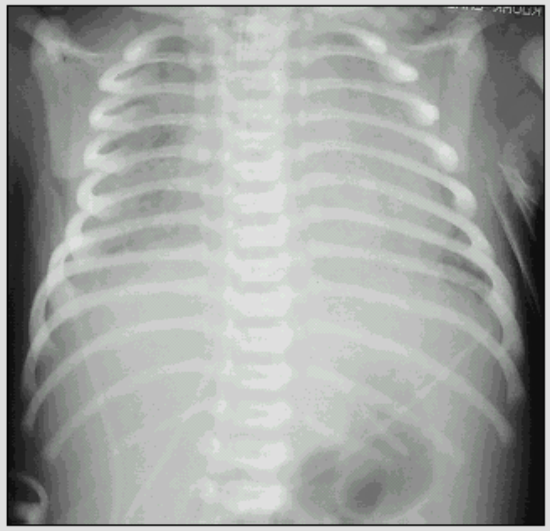

X线胸片

肺纹理粗、肺气肿

斑片状、结节状阴影

纵隔气肿、气胸